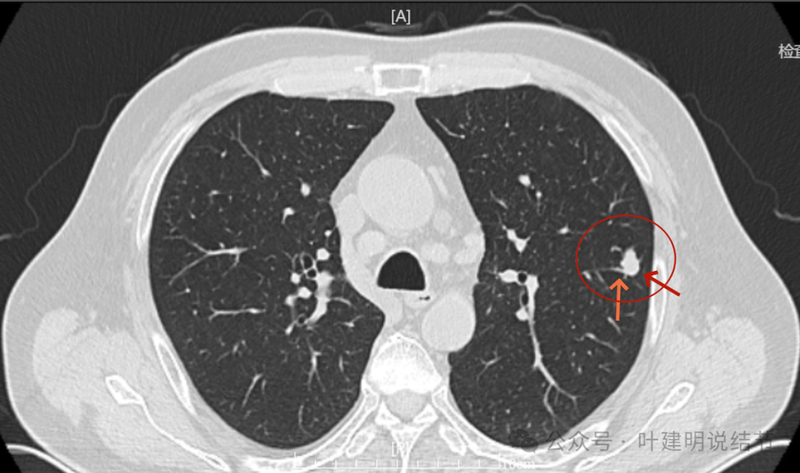

病灶出现,密度较高。

边缘不光滑。

明显实性成分,灶边的细支气管有扩张。

血管与之关系密切,实性密度。

整体有膨胀感,血管有进入病灶。

实性密度并圆形或类圆形,膨胀性明显。

边上有细支气管扩张。

血管进入明显,边缘毛糙不光滑。

血管进入以及表面不平,形态不规则。

少许偏磨玻璃成分,灶边细支气管扩张。

细支气管扩张与实性密度。

边缘区也有细支气管扩张,说明病灶有收缩力,影响邻近细支气管。